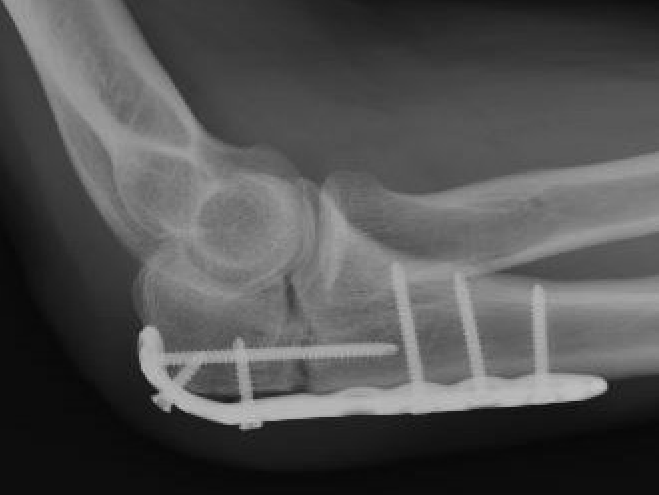

ORIF with olecranon plate

Indication

Fracture distal to center of rotation of elbow / trochlea

Technique

Lateral decubitus with tourniquet

- curvilinear incision to avoid prominence of olecranon

- identify and protect ulna nerve

- reduce fracture with arm in extension

- ensure articular congruity

- use anatomical precontoured plate

- may want to split distal triceps to reduce proximal plate prominence